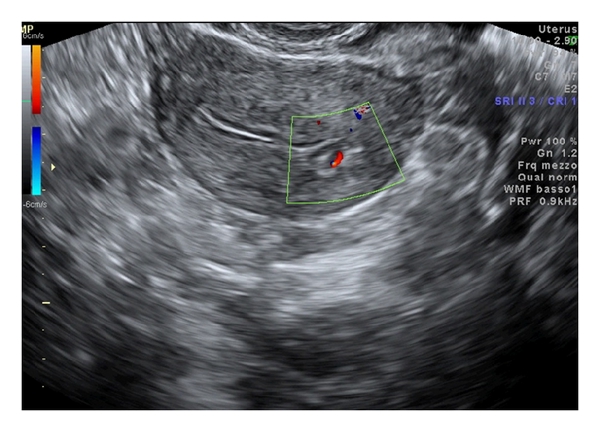

A 38-year-old nulligravida woman presented with metrorrhagia 5 months ago and primary infertility at Outpatient Fertility Clinic of the Second University of Naples. The sonohysterography (Figure 1) showed a 8 × 7 mm-sized echoic nodular mass protruding in the cavity to 60–70%, without abnormal vascularisation. The endometrial implant of the lesion was 5 mm in diameter without infiltration of myometrial layer. The patient underwent diagnostic hysteroscopy that showed a 10 mm-sized yellowish grey lesion localized in the endometrial cavity in proximity of left tubal orifice. A biopsy was performed reaching the pathological diagnosis of endometrial stromal tumor with sex-cord-like differentiation. According to the immunohistochemical results the neoplastic cells were positive for calretinin, desmin, and smooth muscle actin and focally positive for melan A, WT1, inhibin, and Pan-Cytokeratin. The different treatment options were discussed with the patient. A conservative resectoscopic surgery was chosen to preserve fertility, despite the risk of incomplete removal of neoplastic tissue. Surgery was scheduled in the proliferative phase of the next menstrual cycle, reaching apparent complete excision of the lesion (Figure 2). Histological examination and immunohistochemistry confirmed the initial diagnosis of endometrial stromal tumor with sex-cord-like differentiation; such lesion was not classifiable in any subgroup because of fragmentation and small size of the sample. The diagnosis was confirmed without additional elements by two other National Pathological Services. Two months after surgery, a serum pregnancy test resulted positive and the pregnancy continued to progress without complications. At 39 weeks and 3 days an elective caesarean section on maternal request was performed and a healthy baby was delivered. The option for hysterectomy was discussed but the patient refused it. Therefore, a careful follow-up was scheduled performing a transvaginal ultrasound examination every six months and a diagnostic hysteroscopy every year. After 60 months of follow-up, no recurrence was observed.